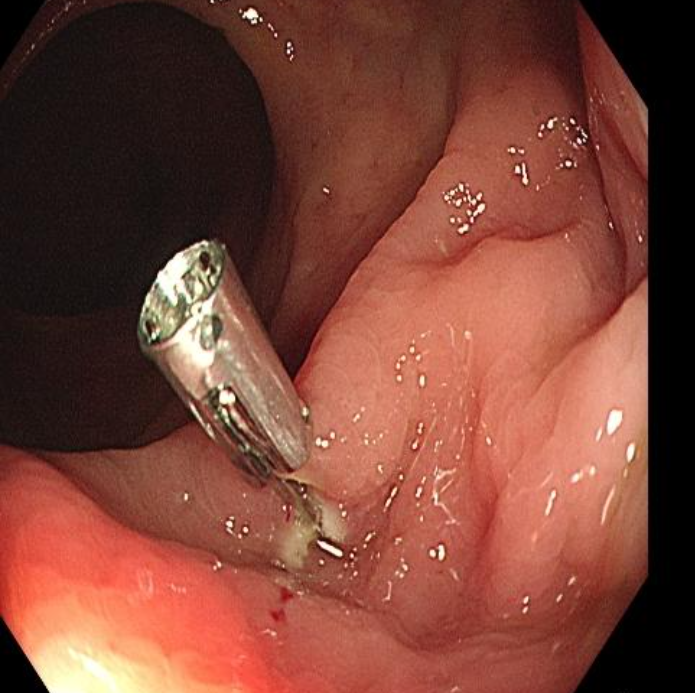

咱们的食管、胃和肠道就像一条长长的 “隧道”,胃肠镜就是医生手里的 “高清摄像头”。通过它,医生能直接看到这条 “隧道” 里有没有破损、长异物,就像给消化道做了一次 “全身扫描”。尤其是无痛胃肠镜,打一针麻醉,睡上十几二十分钟,检查就做完了,等你醒来就像做了场梦,完全没有感觉。柳州东大肛肠医院内镜室主任张利说:“很多患者做完都惊讶,‘这么快就结束了?我怎么啥都不知道!’”

躺在检查床上紧张得不行?别担心!柳州东大肛肠医院的无痛胃肠镜检查,全程有麻醉医生保驾护航,张利主任和他的团队更是经验丰富。检查时,他们会像 “寻宝”一样,不放过任何一个可疑的角落。镜头下,再小的息肉、溃疡都能被发现,还能直接取一小块组织做病理检查,判断是良性还是恶性。